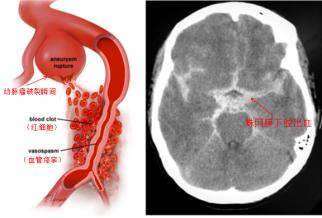

顱內(nèi)動脈瘤并非真正的腫瘤,而是顱內(nèi)動脈壁局部的異常膨出,就像血管壁上鼓起的一個“小氣球” 或“小泡”。這個“小泡” 的壁通常很薄,隨著血流不斷沖擊,它會逐漸變大,當(dāng)壓力超過壁的承受極限時,就會發(fā)生破裂,引發(fā)蛛網(wǎng)膜下腔出血。這種出血來勢洶洶,約30%的患者會在首次破裂后便會直接失去生命,即使僥幸存活,也可能留下偏癱、失語、認知障礙等嚴(yán)重后遺癥,給個人和家庭帶來沉重打擊。